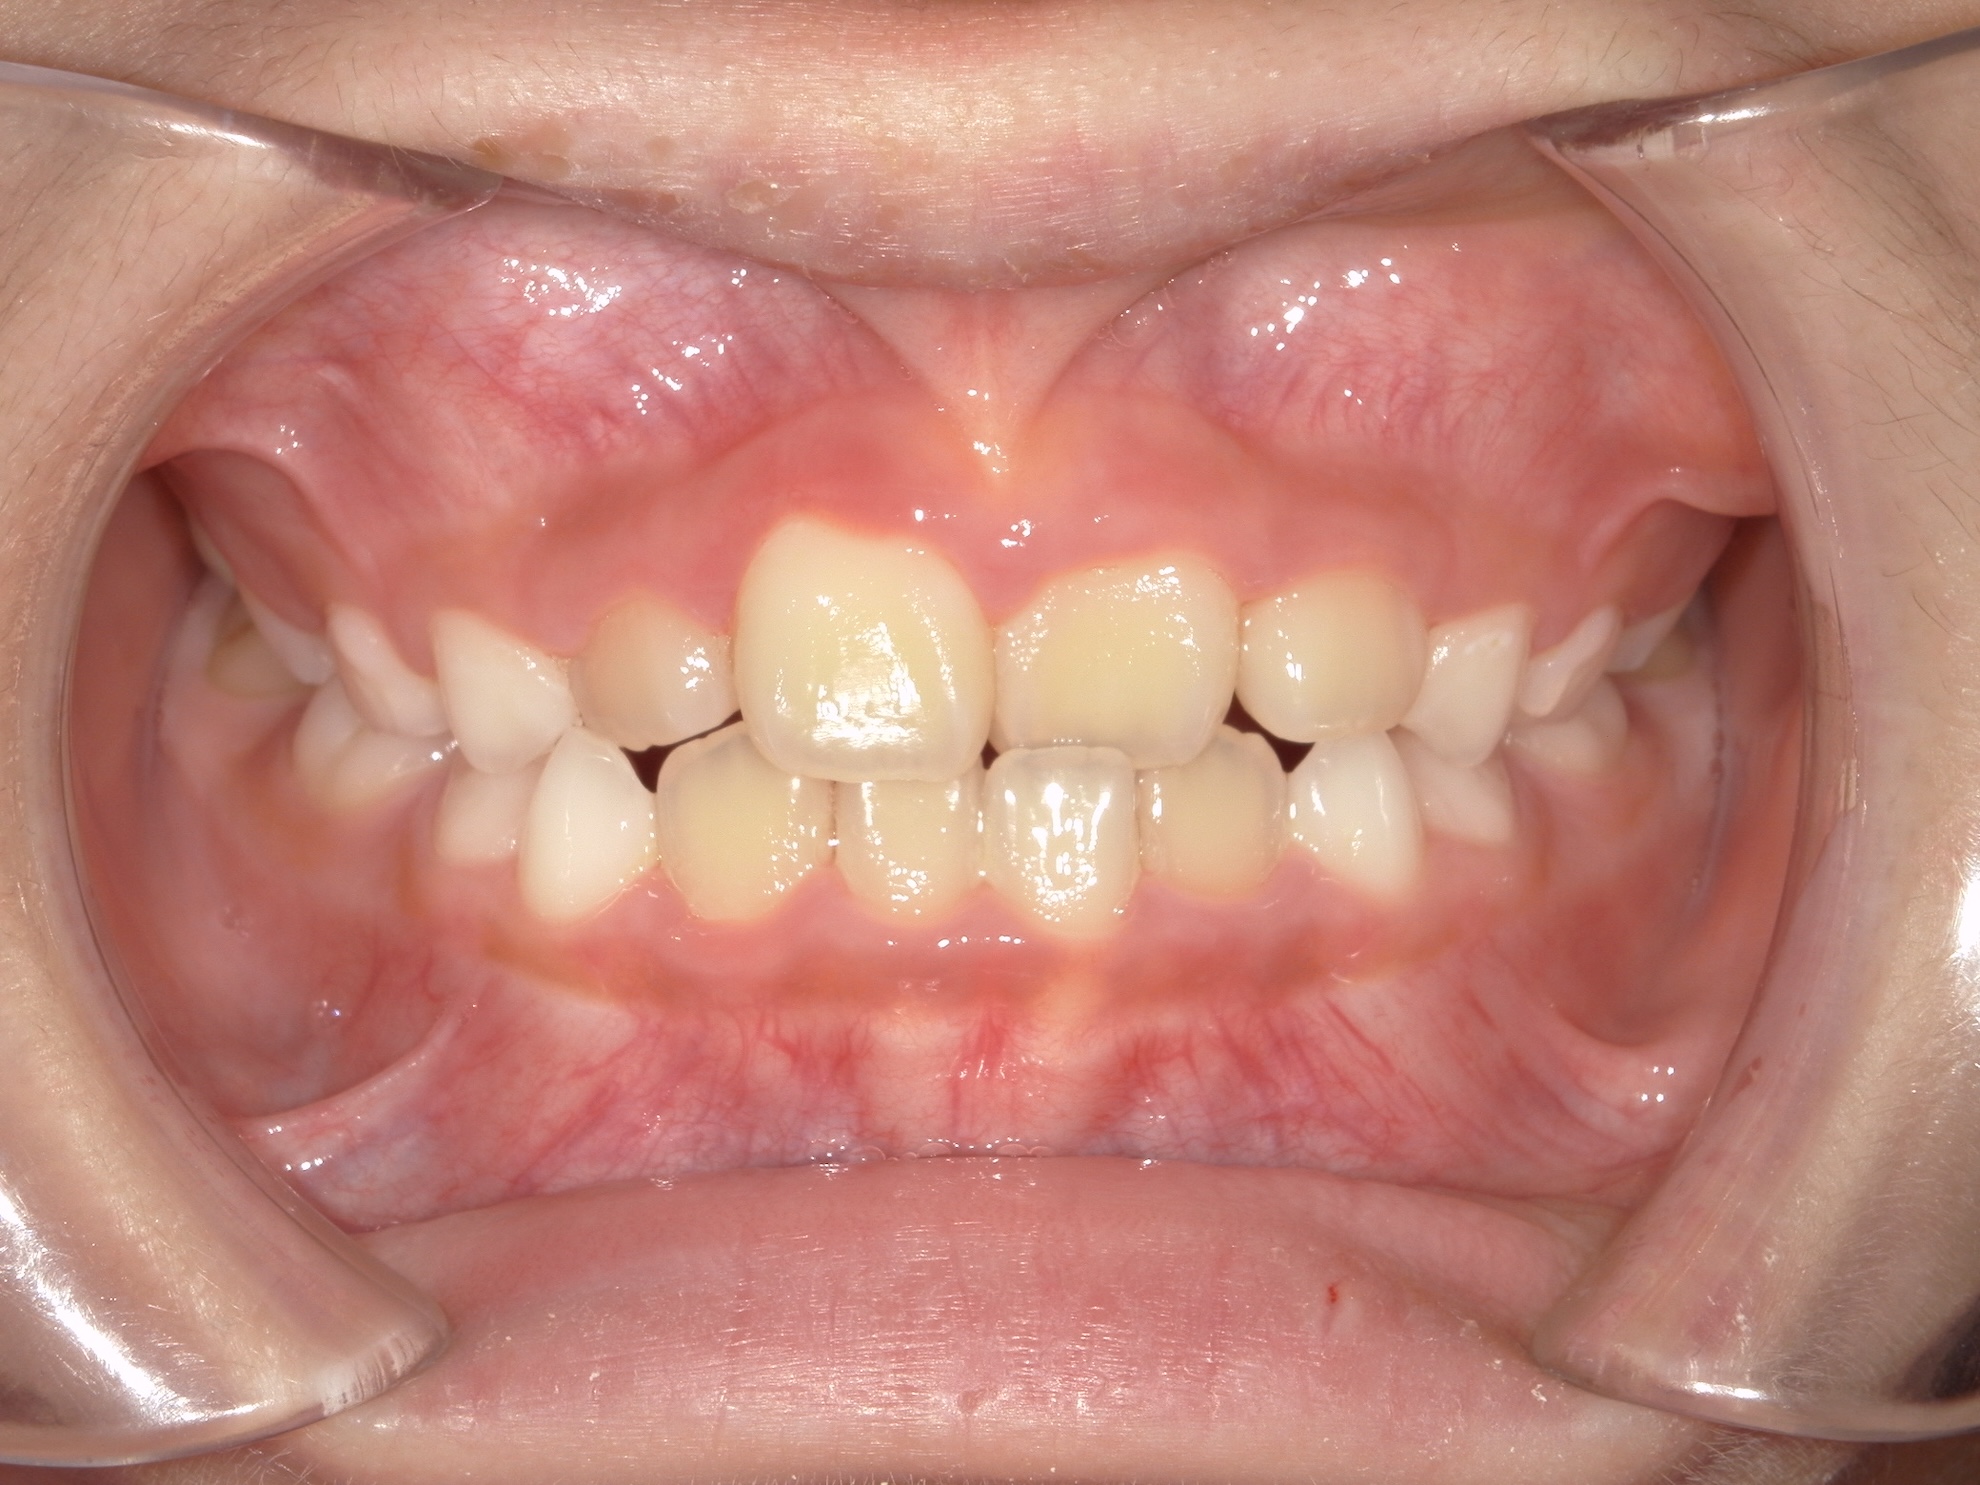

交差している歯並びを改善しました

BEFORE

交差した歯並びの治療前

前歯の歯並びが気になる

骨格性Ⅰ級、歯性Ⅰ級、前歯部クロスバイト(一部)、前歯部叢生

治療内容

拡大床(弾線付き)、部分的な唇側ワイヤー矯正、リテーナー

治療期間

2年半

治療リスク

痛み、歯根吸収

治療費用

約40万円